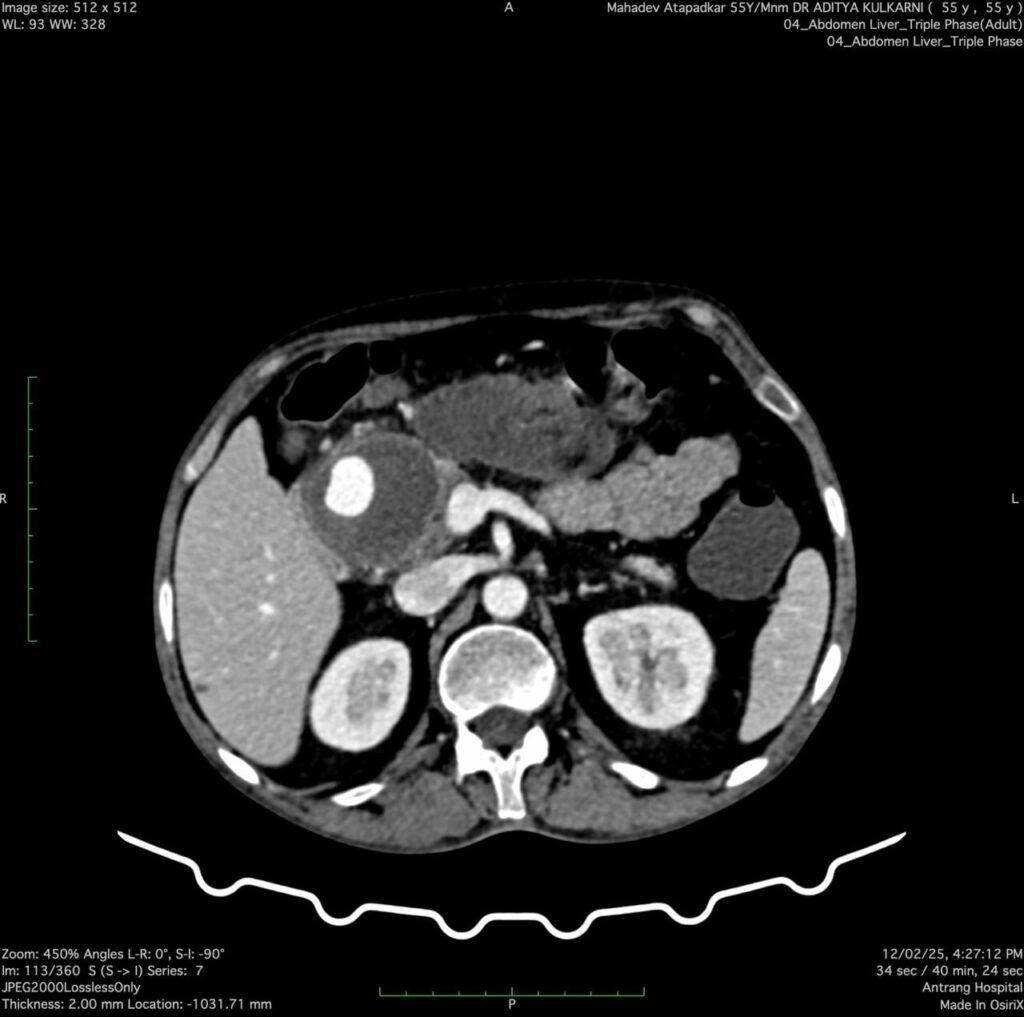

A 53 years- old male presented with a history of repeated GI bleeding for 20days. He had undergone UGI scopy and colonoscopy twice elsewhere with no obvious source of bleed. He was referred to us for further management Initial investigations revealed low haemoglobin levels (3.4), necessitating multiple blood transfusions. CECT abdomen done revealed 4.2×3.4cm pseudo aneurysm arising from Gastro duodenal artery branch within pseudocyst. There was bleeding within pseudocyst. Endoscopic ultrasound (EUS) guided coil +glue was performed to manage the pseudo aneurysm. Post procedure imaging showed Complete Occlusion of the pseudo aneurysm, and the patient was stabilized with supportive care, including IV fluids, antibiotics, and proton pump inhibitors (PPI)

Pseudo aneurysms in chronic pancreatitis are rare but can be fatal due to spontaneous rupture. The primary arteries involved are the splenic, gastroduodenal arteries. The diagnostic approach includes contrast- enhanced computed tomography (CECT), magnetic resonance angiography (MAR), and catheter angiography. Management options include endovascular interventions such as coil embolization or glue injection, surgical resection, or a combination of both as per the local expertise.